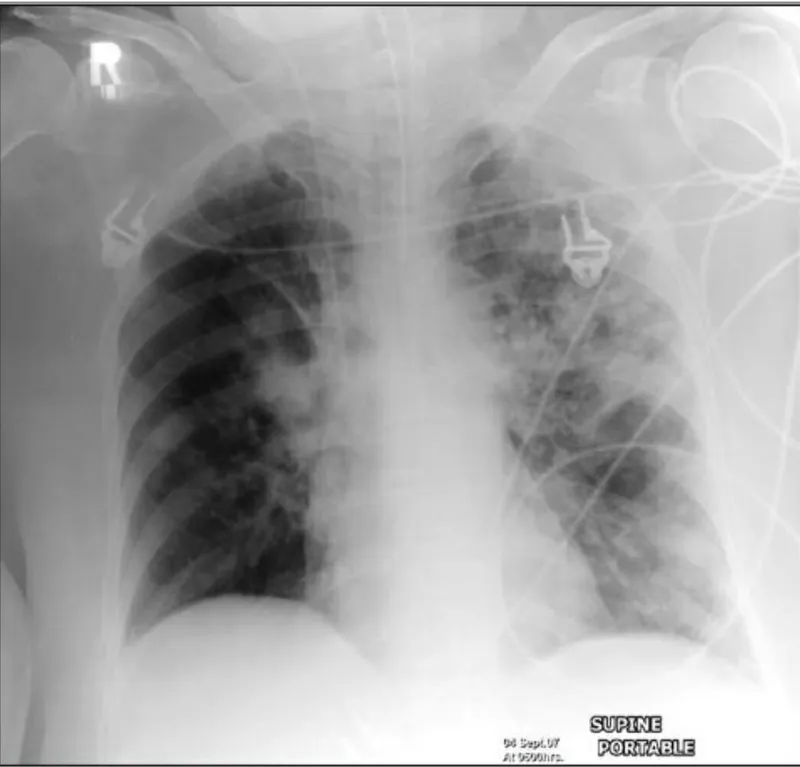

| VAP | New infiltrate | Fever, leukocytosis, purulent sputum | CHF, ARDS | 60-70% sensitivity |